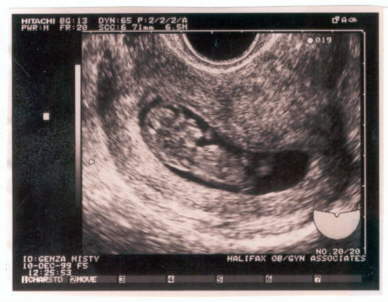

Our first glimpses at our new baby were black and white, grainy, and hard to make out but even then we knew she was going to be beautiful.

Our first look at Madison 5 weeks (10/99).